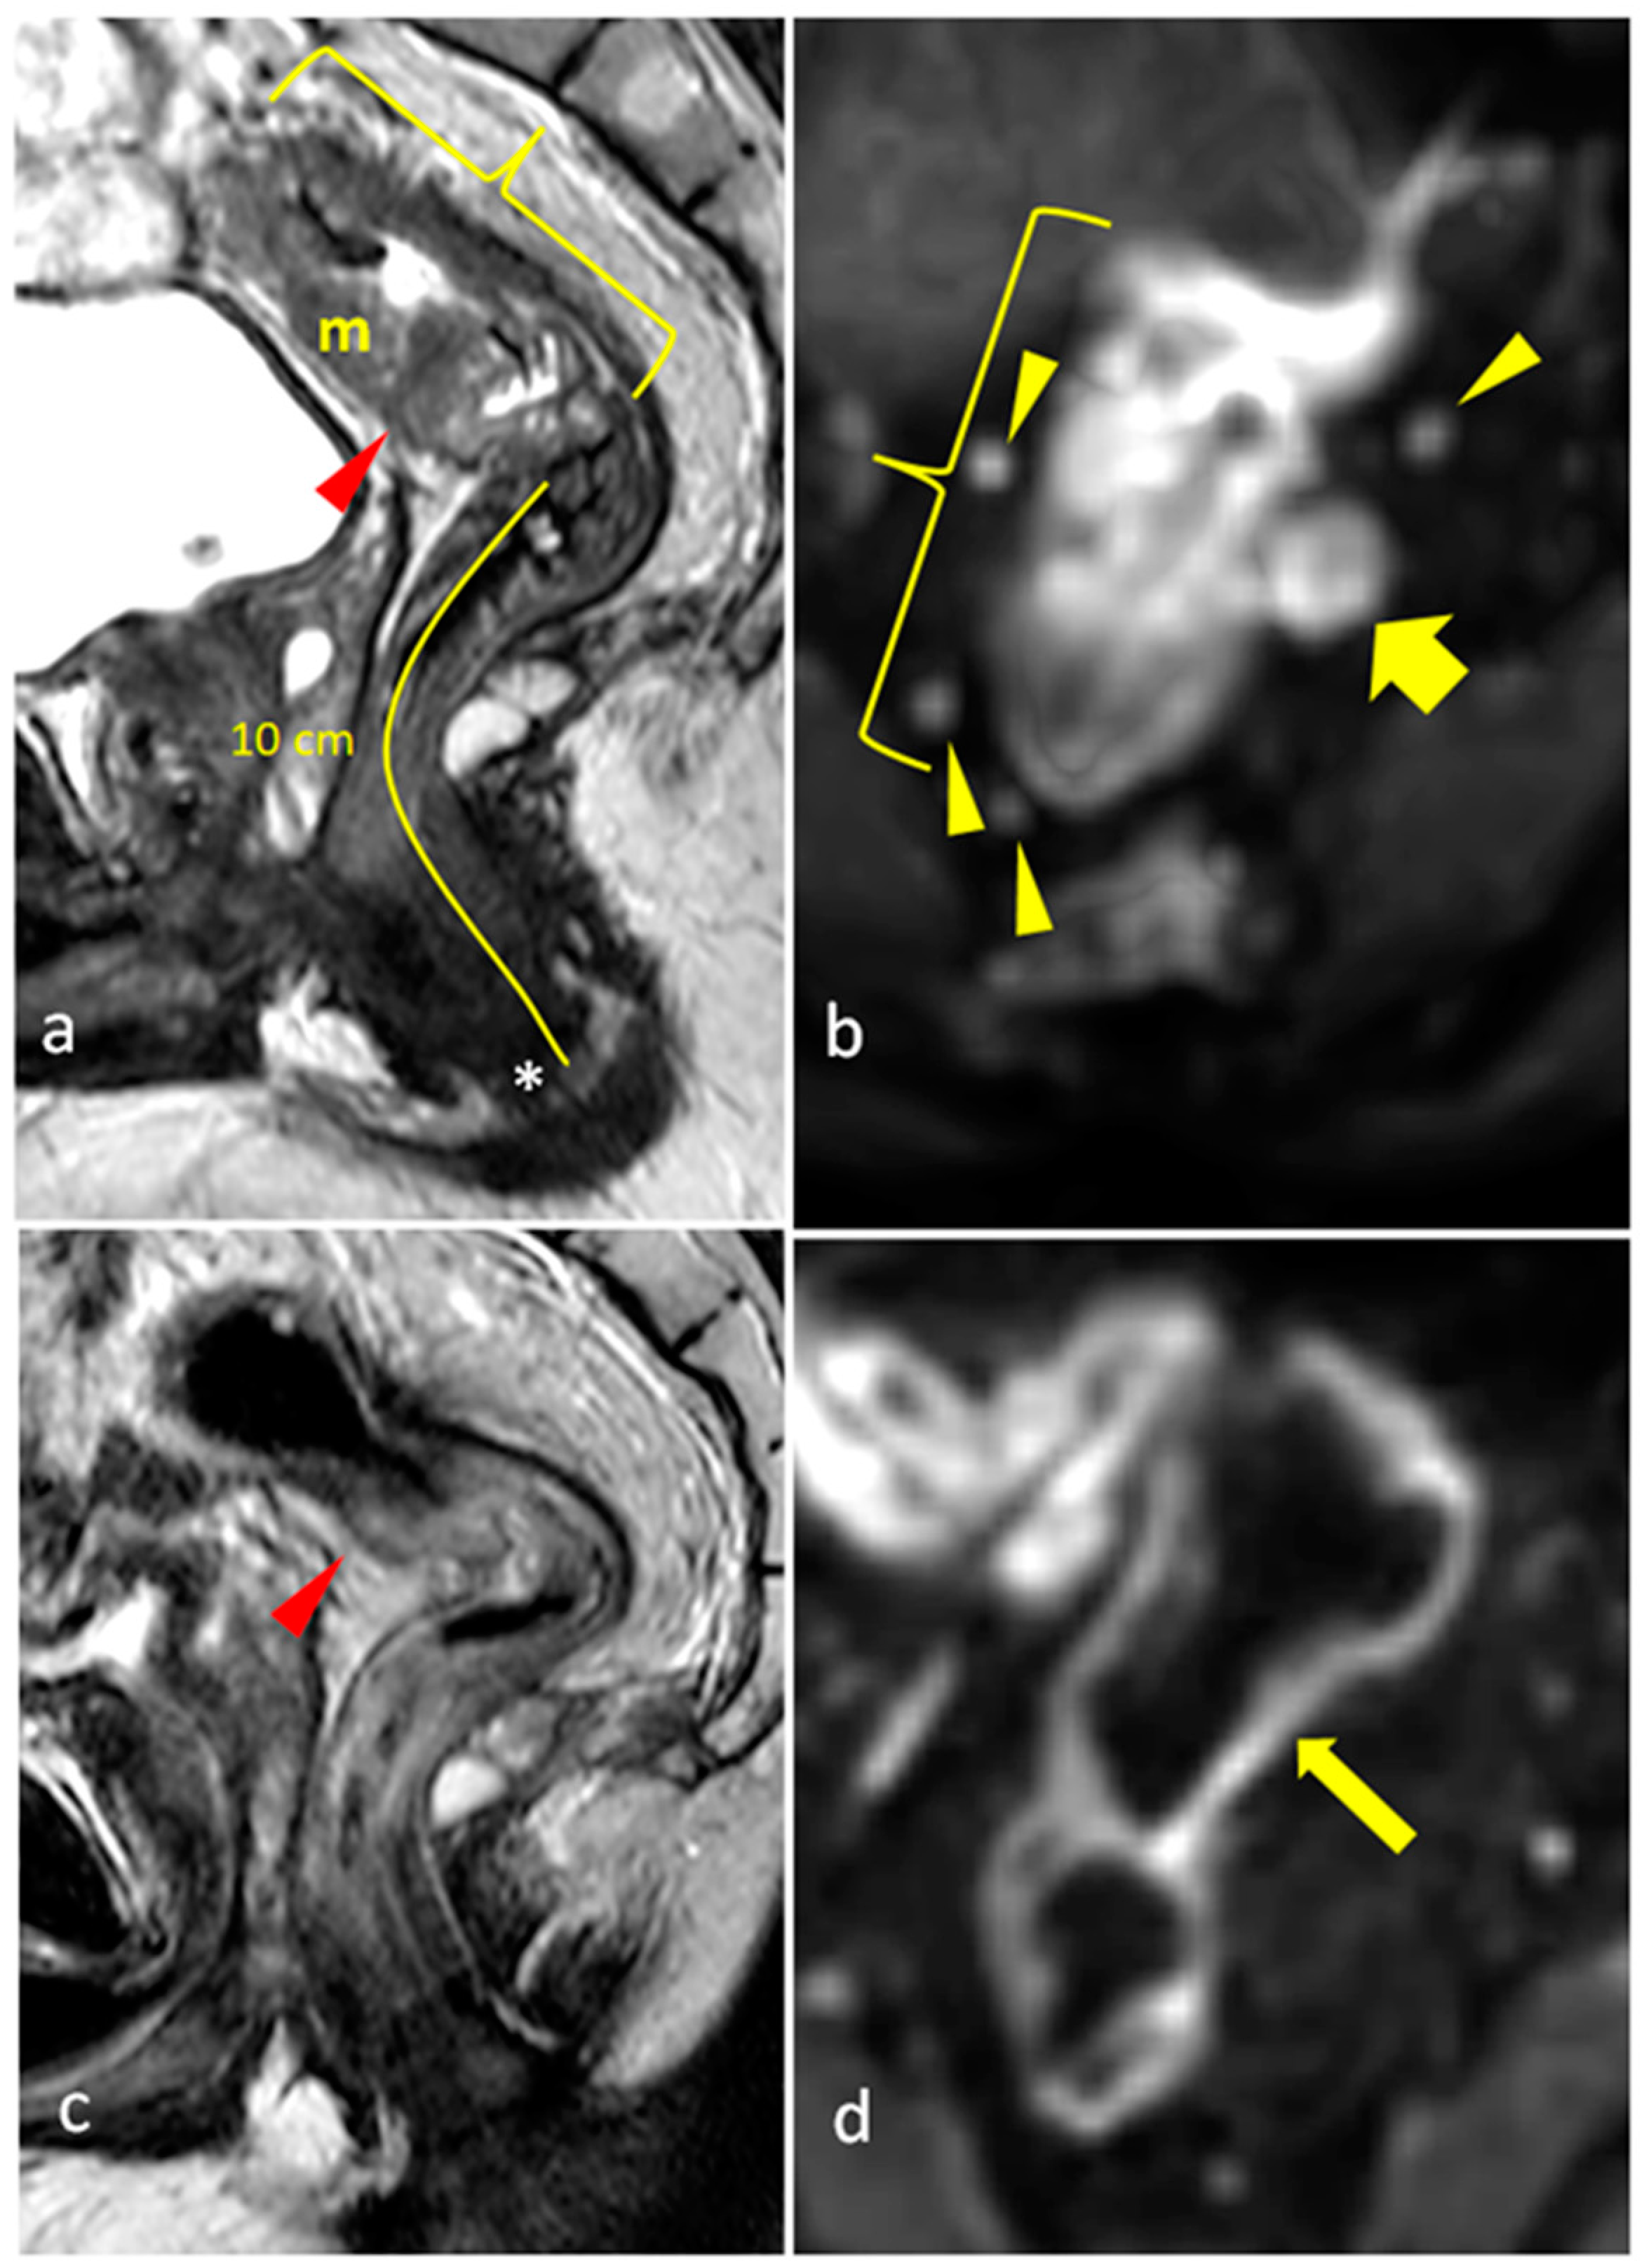

| mrTRG | 1 | Complete Radiologic Response (i.e., no evidence of tumor) |

| 2 | Good Response (i.e., dense >75% fibrosis with no obvious residual tumor) | |

| 3 | Moderate Response (i.e., >50% fibrosis or mucin with a minority of visible tumor) | |

| 4 | Slight Regression (i.e., <50% fibrosis or mucin with a majority of visible tumor) | |

| 5 | No post-treatment changes | |